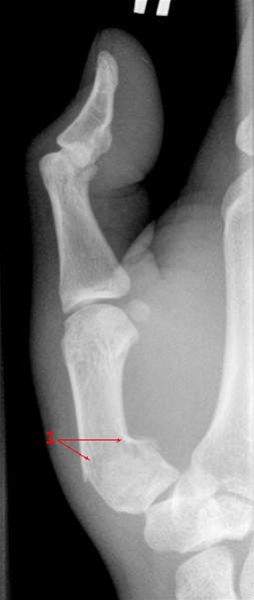

Vinklet fraktur gennem basis af første metakarp (1).

Bruddet er vinklet, og det vil være nødvendig at sætte bruddet på plads i lokalbedøvelse og anlægge gipsbandage. Det er vigtigt at være opmærksom på, at der ved denne type brud kan være tale om en Y-formet fraktur, der går ind i ledfladen (Rolando fraktur), der ofte ikke kan holdes på plads i gips alene. Ved Rolando fraktur er det ofte nødvendig med operation med stabilisering af bruddet med metalstifter (K-tråde).